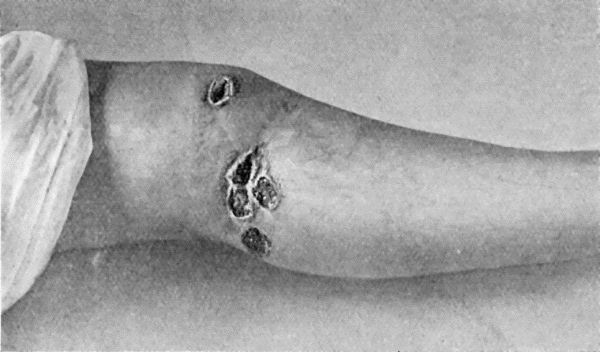

17.Syphilitic Ulcers in region of Knee 76

42.Tertiary Syphilitic Ulceration in region of Knee and on both Thumbs 171